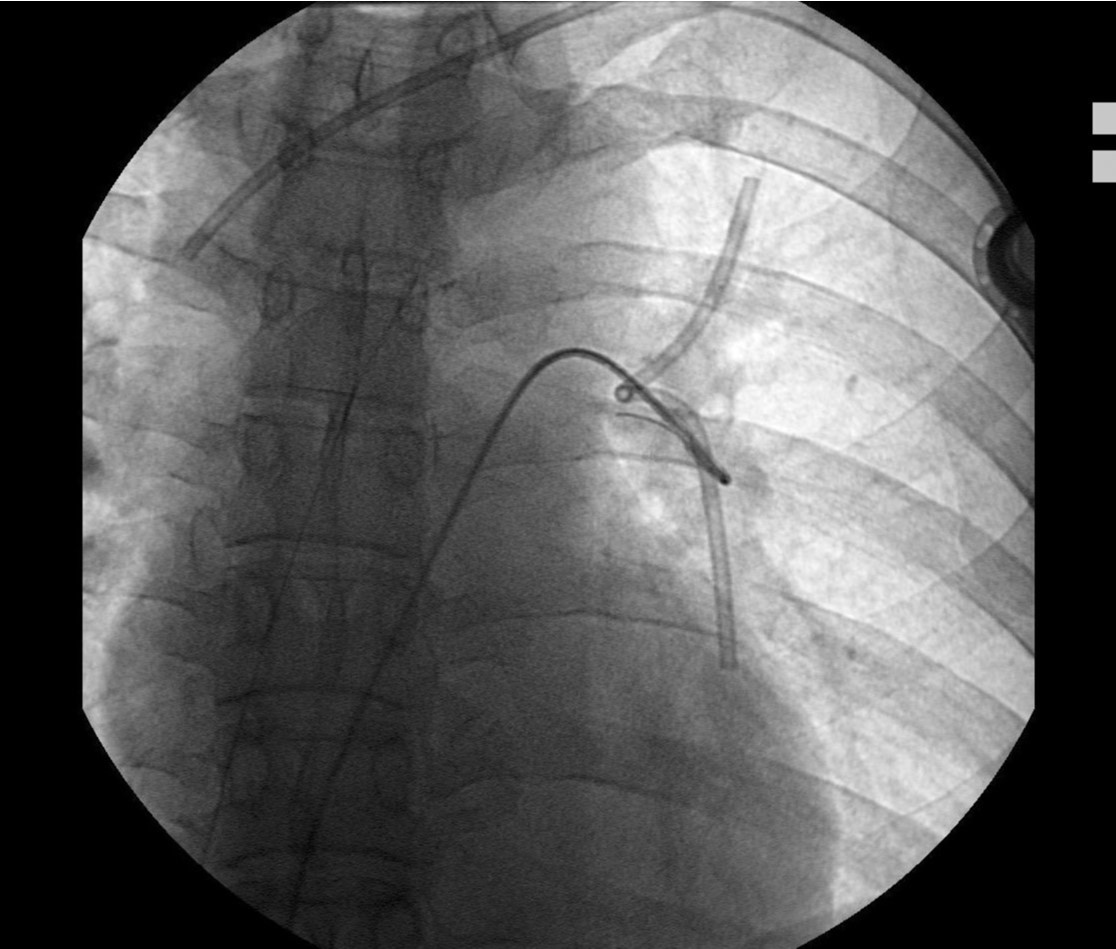

Fig. 4. C

(C) Snaring of fragmented chemoport tube and pigtail catheter together.